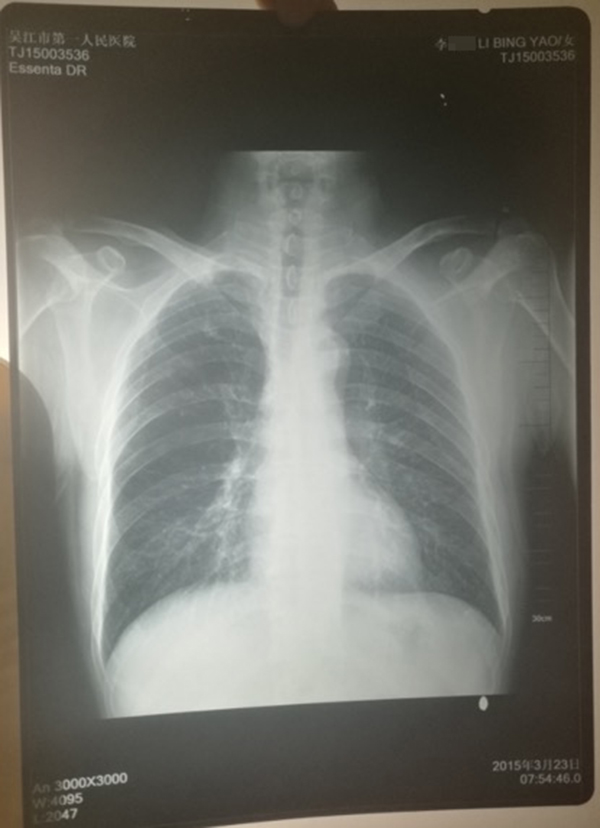

ݐ@2015e323Iqb͕o[Ò˥|YypҳܐޣI̮ڨYĒnLlRڱ`

ݐ2015e3@YypҳܡLlRڱ` k